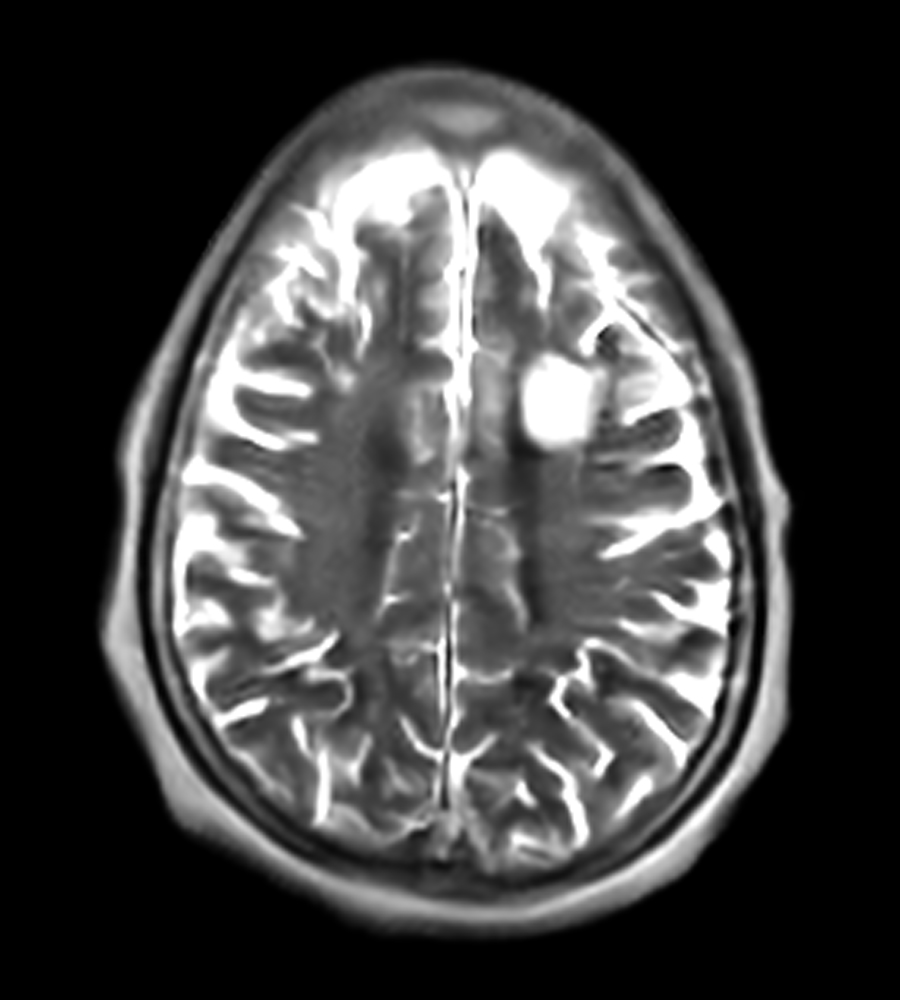

Clinical Images

Clinical Case Types: Headache, Migraine, Multiple Sclerosis, Microvascular Disease, and Tumor Routine Follow-up.

Migraine